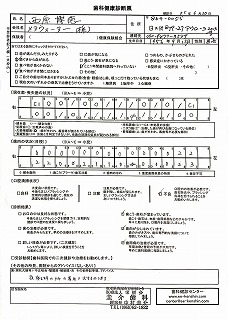

2023.06.30より 圭介歯科 0968-62-1822

23.7.21 検査 PDF

23.10.27 検査 PDF

23.10.27 検査 PDF

⑤ 2021.09.11 Sat.遠山歯科 診断.jpg

④2020.10.09 Fri.遠山歯科 歯周診断.jpg

③2018.09.12 Wed. 遠山歯科初診 歯周診断=PDF